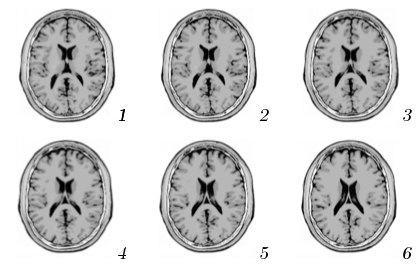

The databases used in our experiments are a T2-modulation volume MRI cut into slices along the directions, from the Brainweb simulator [6] and the ORL Database of faces [11]. In order to test the ISH, three sets of transformations have been applied on these images: (i) 9 rotations of angles between and , (ii) scalings of factors between and , (iii) and 9 random combinations of these rotations and scalings. A schematic illustration of the face image manifold (that has a polar representation for each image) is shown in Fig. 1.

is an increasing function of for sufficiently close to zero. Fig. 4 shows the evolution of (with two dashed curves providing the 99% confidence interval on estimation) computed over the 100 brain slices rotated and scaled. The expectation of the distance is indeed increasing for . This means that the distance between ISH truly reflects the difference between visual contents. The MRI was indeed taken with a resolution of 1mm for which visual contents of contiguous slices are very close, as depicted in Fig. 4. The false positive pairs of images are therefore more likely to be adjacent slides which are visually close than totally different slides.